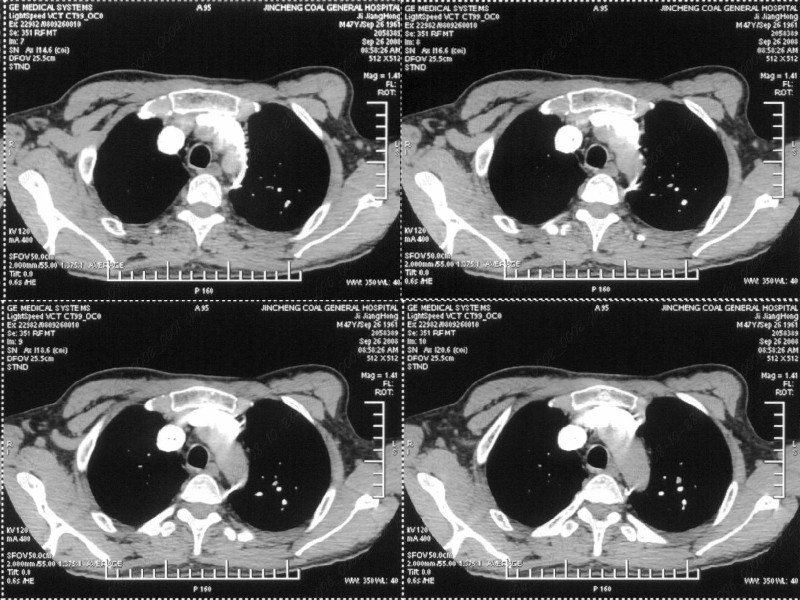

图像很清,资料很全。工作做的很细,向您学习!观阁下的强化图像发现,您们强化后扫描时间挺早,延迟时间大约在16—18秒之间吧。估计目的是为了观察肺动脉及分支的情况。但现有的资料并不能提示动脉栓塞改变。建议楼主可在机器上仔细观察,或许会有异常发现。另外,个人感觉右侧应为肺内结节而非胸膜结节。考虑肺内良性小结节,炎性假瘤可能性大。

汇报临床诊断:右肺动脉分枝栓塞

右肺静脉充盈缺损,左心房体积小,右肺动脉远端动脉充盈缺损,右肺血管影细小,考虑;右肺动脉远端栓塞.